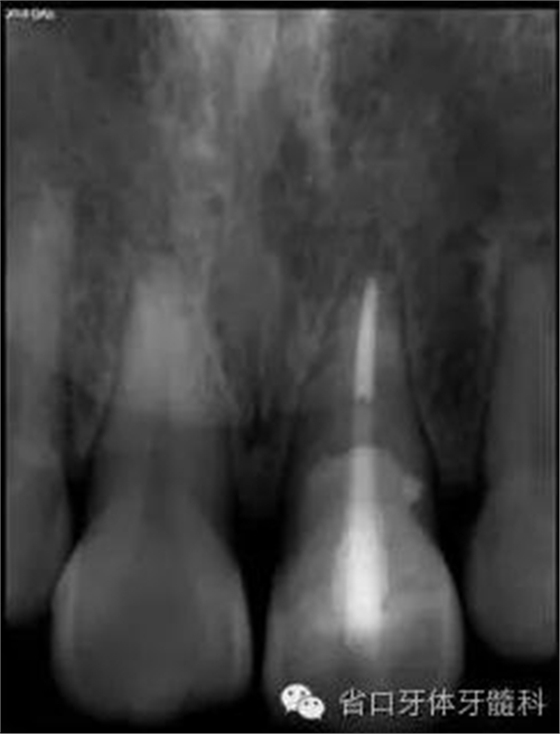

圖3. 術前X線片

圖8. 21/行根管治療術,保留根尖約5mm的根充物,根中上段預留空間以預備纖維樁道。

圖17. 術后X線片